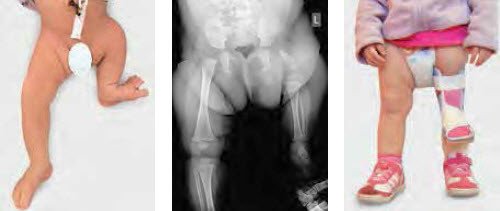

Die Therapie richtet sich grundsätzlich danach, ob die betroffene Extremität überhaupt sinnvoll rekonstruierbar ist. Schwere Gelenk- und Fussdeformitäten sowie höchstgradige Beinlängendifferenzen können rekonstruktiv-chirurgische Massnahmen infrage stellen, so dass orthoprothetisch vorgegangen werden muss (Abb. 3–5). Ist ein rekonstruktives Verfahren möglich, ist zunächst dafür Sorge zu tragen, dass insbesondere an den benachbarten Gelenken möglichst stabile Verhältnisse für bevorstehende Verlängerungsoperationen geschaffen werden.

Die chirurgisch-rekonstruktiven Massnahmen umfassen teilweise eine Vielzahl an Einzelschritten, wobei das Ziel ist, bis zum Wachstumsabschluss die Behandlung beenden zu können. Dem behandelnden Spezialisten wie auch dem betroffenen Kind und dessen Eltern muss die Tragweite der möglicherweise sehr langwierigen und aufwendigen Therapie bewusst sein. Bei schweren Fehlbildungen sind mehrere Verlängerungsoperationen mit externen Fixateuren neben diversen kleineren Eingriffen an Gelenken und Füssen die Regel und haben sicher Einfluss auf die Entwicklung des Kindes. Die langwierige Therapie und nicht zuletzt die hohen Kosten werden insbesondere im angloamerikanischen Sprachraum als Argument für amputative Massnahmen bei hochgradigen Deformitäten angegeben. In unserem Sprachraum stossen Amputationen grundsätzlich auf Ablehnung; mit neuen und ständig verbesserten Rekonstruktionsverfahren und -techniken können diese auch meistens vermieden werden.